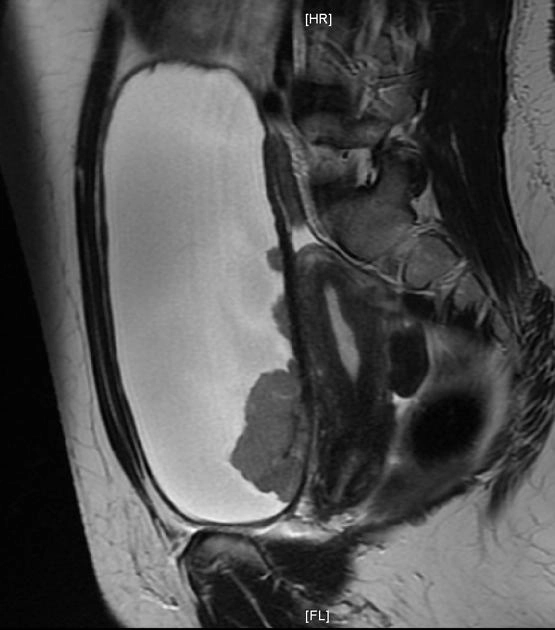

• Khối u bàng quang

U cơ trơn bàng quang (Leiomyoma of the urinary bladder)

Ung thư biểu mô tế bào chuyển tiếp ở bàng quang (Transitional cell carcinoma (urinary bladder))

Phân loại giai đoạn ung thư của bàng quang (Transitional cell carcinoma of the bladder (staging))

Ung thư biểu mô tuyến của bàng quang (Adenocarcinoma urinary bladder)